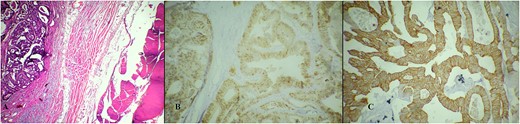

A 73-year-old female patient was admitted to our hospital due to the existence of a tumor in the abdominal wall proved to be a metachronous adenocarcinoma metastasis. In October 2015, the patient was treated for rectosigmoid adenocarcinoma when rectosigmoid resection with primary anastomosis was performed. Pathology report revealed tumor stage I (pT2, pN0, pM0, pL0, pV0, pR0, G2, NG2). Only three lymph nodes were harvested and reported to be negative by the pathologist. Nevertheless, the oncologist decided not to initiate adjuvant chemotherapy, and recommendations for routine outpatient check-ups were advised. Two postoperative routine colonoscopies with normal findings were performed (in 2016 and 2022). Shortly after the second colonoscopy (in September 2022), elevated values of serum tumor markers were detected: Carcinoembryonic antigen (CEA) value of 15.2 ng/mL and Carbohydrate antigen (Ca) 19–9 value of 47.3 U/mL. The oncologist initiated adjuvant treatment with eight cycles of oxaliplatin and capecitabine. In March 2023, the additional elevation of markers followed (CEA value of 58.64 ng/mL, Ca 19-9 value of 665.12 U/mL, and Cancer antigen 15-3 value of 32.5 U/mL). In June 2023, serum marker levels decreased (CEA value of 35.5 ng/mL and Ca 19-9 value of 147 U/mL). Physical examination on routine follow-up revealed a palpable painless mass in the midline suprapubic region without skin involvement. Abdominal computerized tomography presented a solid tumor mass in the abdominal wall with dimensions of 70 × 40 × 80 mm and it was described as a suspected metastatic deposit by the radiologist (Figs 1 and 2). Core biopsy under ultrasonography guidance confirmed the presence of metastatic adenocarcinoma ˃7 years after the primary colon cancer surgery. A decision upon surgical removal was brought. The lesion was excised (Figs 3 and 4) and the defect of the abdominal wall was reconstructed by the use of composite mesh (Fig. 5). The postoperative course was uneventful and the duration of stay was 7 days. The pathology report confirmed the presence of metachronous metastasis from colon adenocarcinoma. Metastasis was measured to be 10 × 6 × 5 cm, completely occupied by a neoplastic infiltrate (Fig. 6). Immunohistochemistry staining showed positivity on Caudal-type homeobox 2 (CDX2) and Cytokeratin 20 (CK20) thus proving the origin of the metastatic deposit from colorectal adenocarcinoma (Fig. 7A–C).

Microscopic pathology analysis of the metastasis. (A) Hematoxylin Eosin stain showing metastatic infiltrate of adenocarcinoma into soft tissue (abdominal wall muscle). (B) Immunohistochemistry stain showing positivity on CDX2. (C) Immunohistochemistry stain showing positivity on CK20.